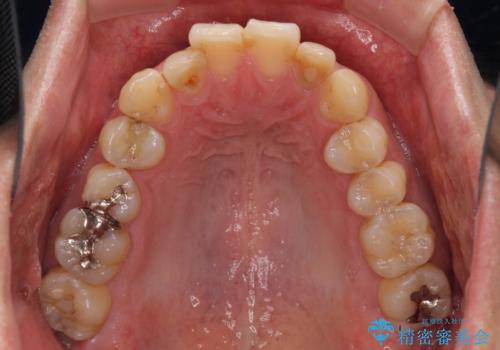

前歯のデコボコと下顎の八重歯 インビザラインによる矯正治療

- 前歯のデコボコや八重歯を気にして来院された患者様です。

インビザラインを用いて、歯列を整えることとしました。

下顎前歯は後戻りを起こしやすいため、舌側を細いワイヤーで固定し、マウスピース型リテーナーで保定を行うこととしました。